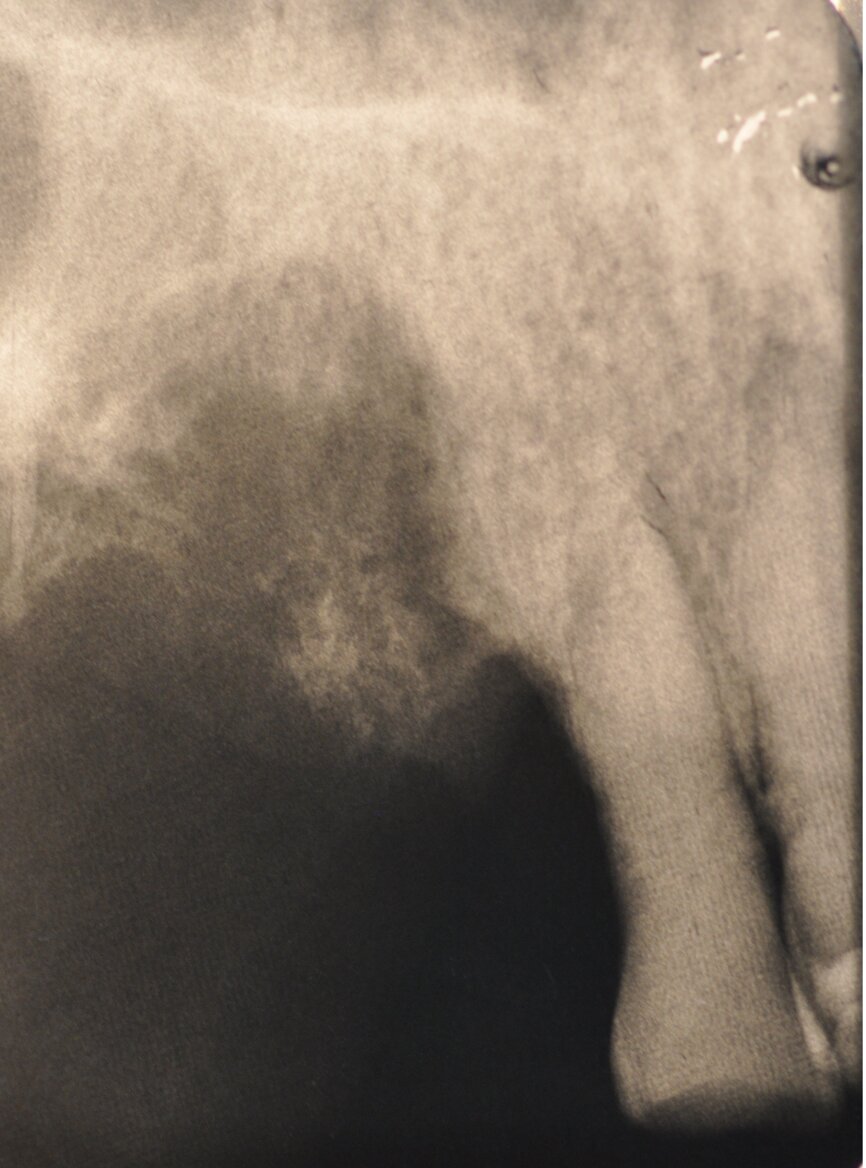

Ryc. 1-3_Stan przed leczeniem: 2. Zdjęcie rtg okołowierzchołkowe